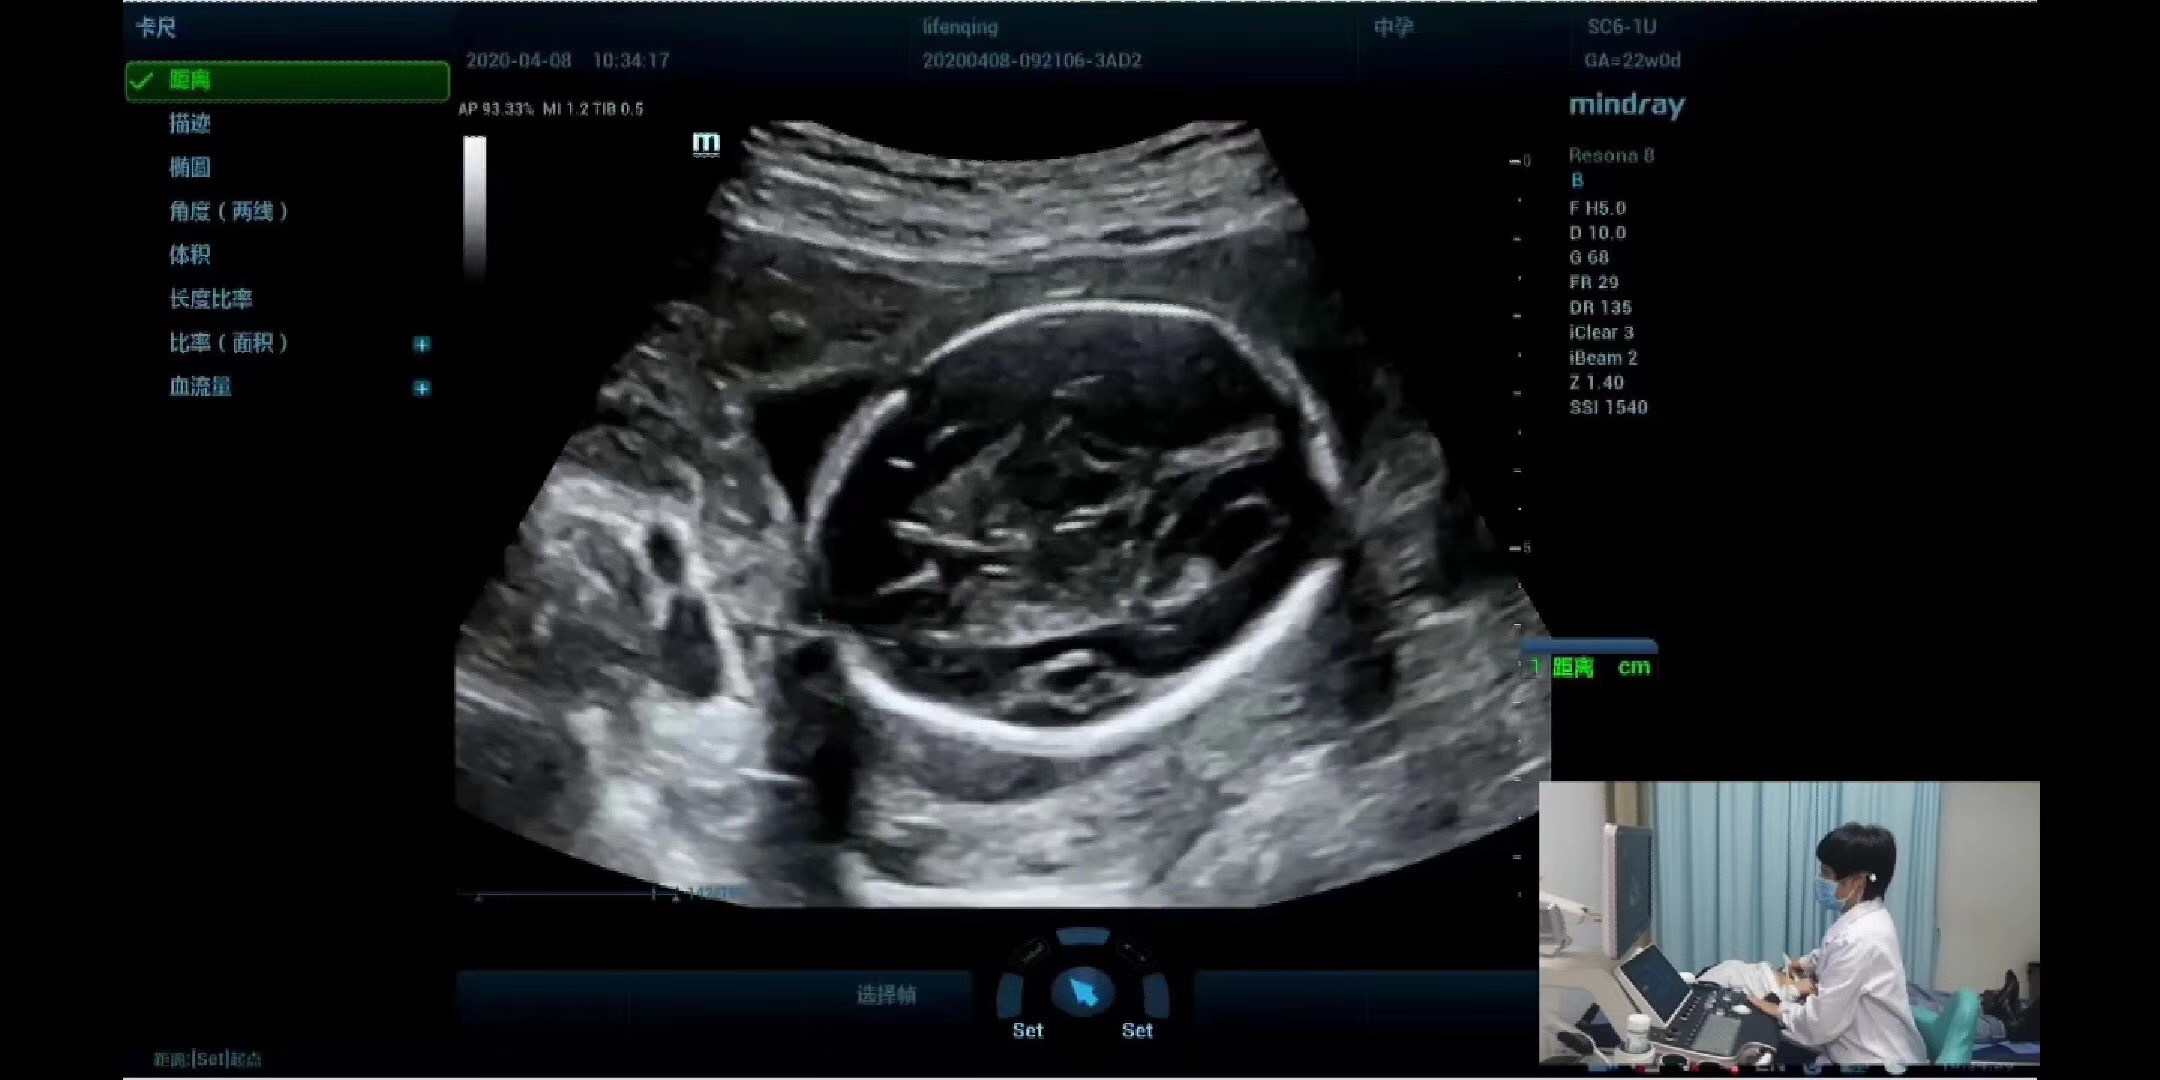

本次会议内容包括病例分享、操作规范演示、超声诊断能力擂台赛。会议期间,省内心脏、妇产超声专家分享了疑难病例的超声诊断分析思路,并对心脏、妇产超声检查标准切面及规范操作进行了在线演示,同时连线了支援湖北的甘肃超声医师协会副会长、940医院超声科副主任任小龙教授。任小龙教授与大家积极分享了武汉经历和感人视频,增加了疫情防控期间爱国主义和防控知识的教育。

会议同时进行了心脏、妇产超声诊断能力擂台赛,来自甘肃省市州县共60家医院(省级医院的有2家,市州级医院41家,县级医院17家)的240名超声医师参加了比赛。擂台赛内容包括:标准切面考核、超声诊断理论考核、病例诊断考核,比赛在2个半小时的在线答题中结束,随后省内12位专家分别对于单选题、多选题、病例分析题的标准答案进行了解析。会议最后,聂芳教授做了总结致辞。